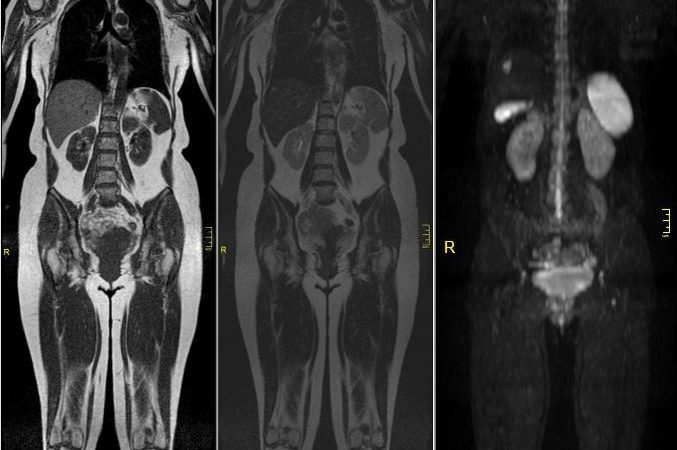

• DAG ile beyindeki serbest su protonlarının uygulanan difüzyon gradyenti boyunca yaptığı hareket ölçülür.Bu hareket daha makroskopik olduğundan görünür difüzyon olarak tanımla nır ve sabit bir katsayı ile (ADC) ölçülebilir.

Difüzyon uygulamalarda B değeri ve ADC haritalandırma:

ADC(ortalama difüzyon katsayısı)belirleyebilmek için en az 2 farklı difuzyon gradyentlerine maruz kalmış serilere ihtiyaç duyarız.B değeri difüzyon duyarlılığını saptamakta kullanılır.B değeri 0 olduğunuda T2 ağırlıklı imaj ile aynı olur.B değeri arttıkça difüzyon ağırlığı artar. B0 gradyentli datalar ile B 1000(beyin için) gradyentli datalar ana bilgisayrda işlenerek ortalama difüzyon katsayısı hesaplanabilir.

Sağ temporal lobda akut iskemiye sekonder ADC görüntülerde difüzyon kısıtlanması.

Akut inme şüphesi ile gelen hastalara önce difüzyon sekansı alınmalıdır.Hastanın duramama veya durumunun kötüleşmesi gibi durumlarda hastanın tetkikini sona erdirmek gerekiyorsa en azından elimizde difüzyon gibi değerli bir data olur.Ancak diğer stabil durumlarda mutlaka konvansiyel (Flair veya T2) sekans serilerini almamız;  iskeminin oluş zamanını değerlendir -memizde  yardımcı olacaktır.Bu da tedavi sürecini direkt olarak etkileyecek faktörlerdendir.